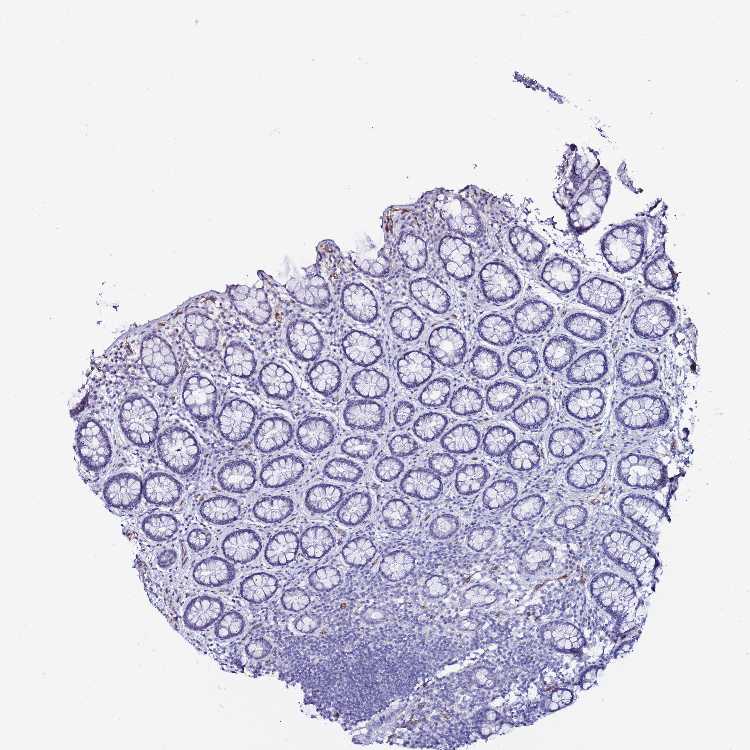

DEFB104A